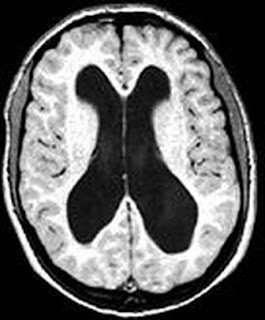

Erkennbar sind die mit Flüssigkeit gefüllten Ventrikel (schwarze Fläche, Bild oben). Normalerweise weist die Gehirnrinde eine Dicke von etwa 4 Zentimetern auf, bei ihm war sie jedoch auf die Dicke eines Papierblattes zusammengeschrumpft. Dr. Lorber schätzte, dass das gesamte Gehirn des Mannes nur etwa 100 Gramm wog. Ein normales Gehirn eines Erwachsenen wiegt zum Vergleich etwa 1,3 Kilogramm, also 13-mal soviel. Der Student litt unter einem Wasserkopf, einer Krankheit, bei der die Gehirn-Rückenmark-Flüssigkeit anstatt um das Gehirn zu zirkulieren und anschließend in den Blutstrom überzugehen, im Inneren aufgestaut wird.

Gemäß neuropsychologischen Untersuchungen habe der Mann einen Intelligenzquotienten (IQ) von ca. 75. Der Durchschnitt liegt heute bei ca. 100. Bei den Untersuchungen habe sich gezeigt, dass die üblichen Hohlräume im Gehirn sich bei dem Mann massiv ausgedehnt hätten, sagte Feuillet. Trotz allem ist er nahezu normal entwickelt und hat sich ein soziales Netz aufgebaut.

«Das Gehirn selbst, also die graue und weiße Nervenmasse, war völlig -wie eine Schale- an den Rand des Schädels gedrückt.» Der zweifache Vater habe trotzdem ein normales Leben geführt.